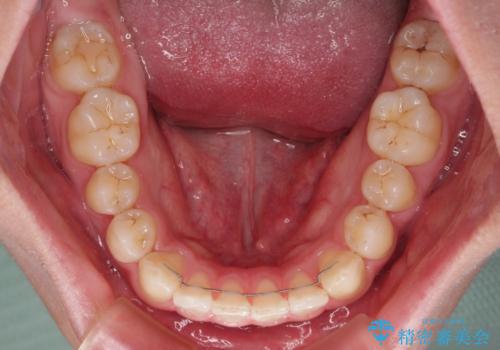

隙間とデコボコを治したい ワイヤー装置による矯正治療

- 前歯のデコボコと隙間を気にして来院された患者様です。

治療手段としてはワイヤー装置でもインビザラインでも可能でしたが、インビザラインの自己管理は自信がないとのことで、ワイヤー矯正により隙間を閉じていくこととしました。

舌の突出癖がなかなか改善されず、治療開始時よりも隙間が大きく開いてしまう時期がありましたが、最終的にしっかりと閉じて終了することができました。